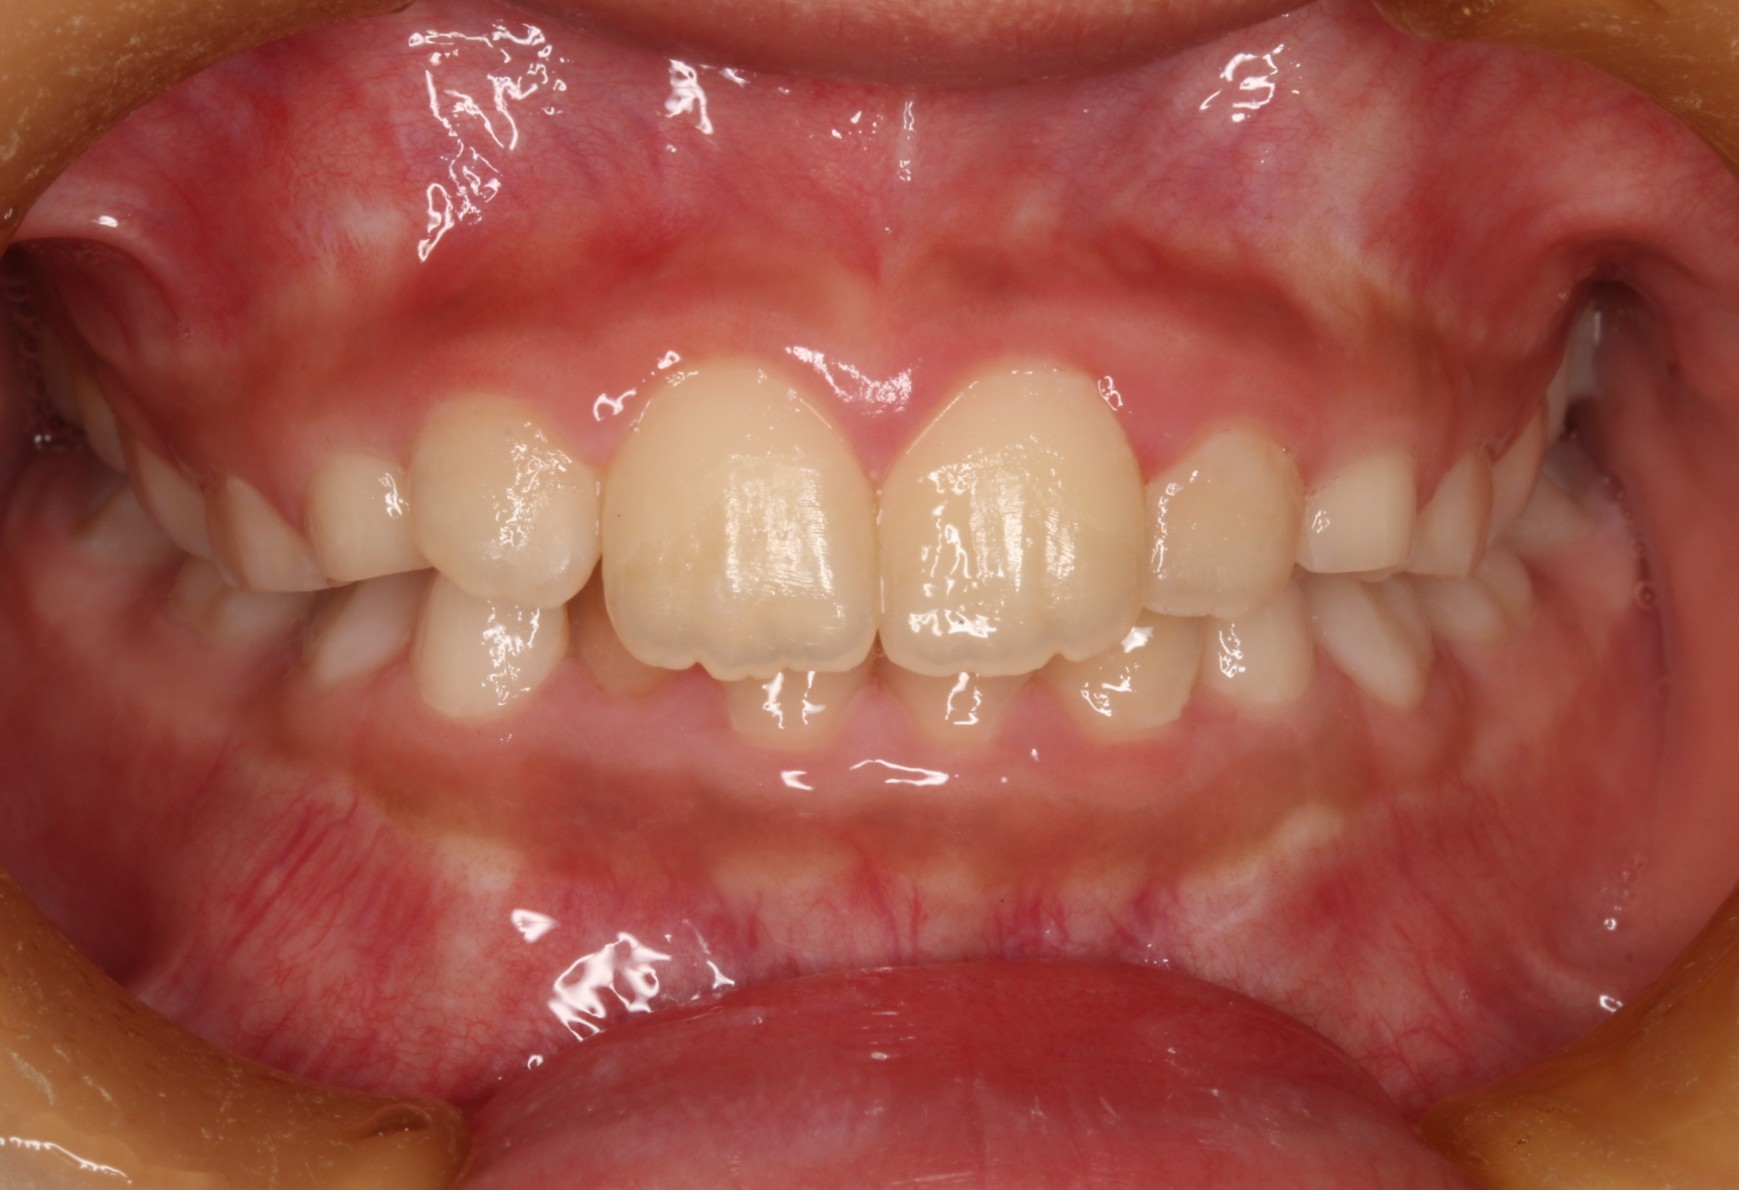

矯正術前:正面

矯正術後:正面